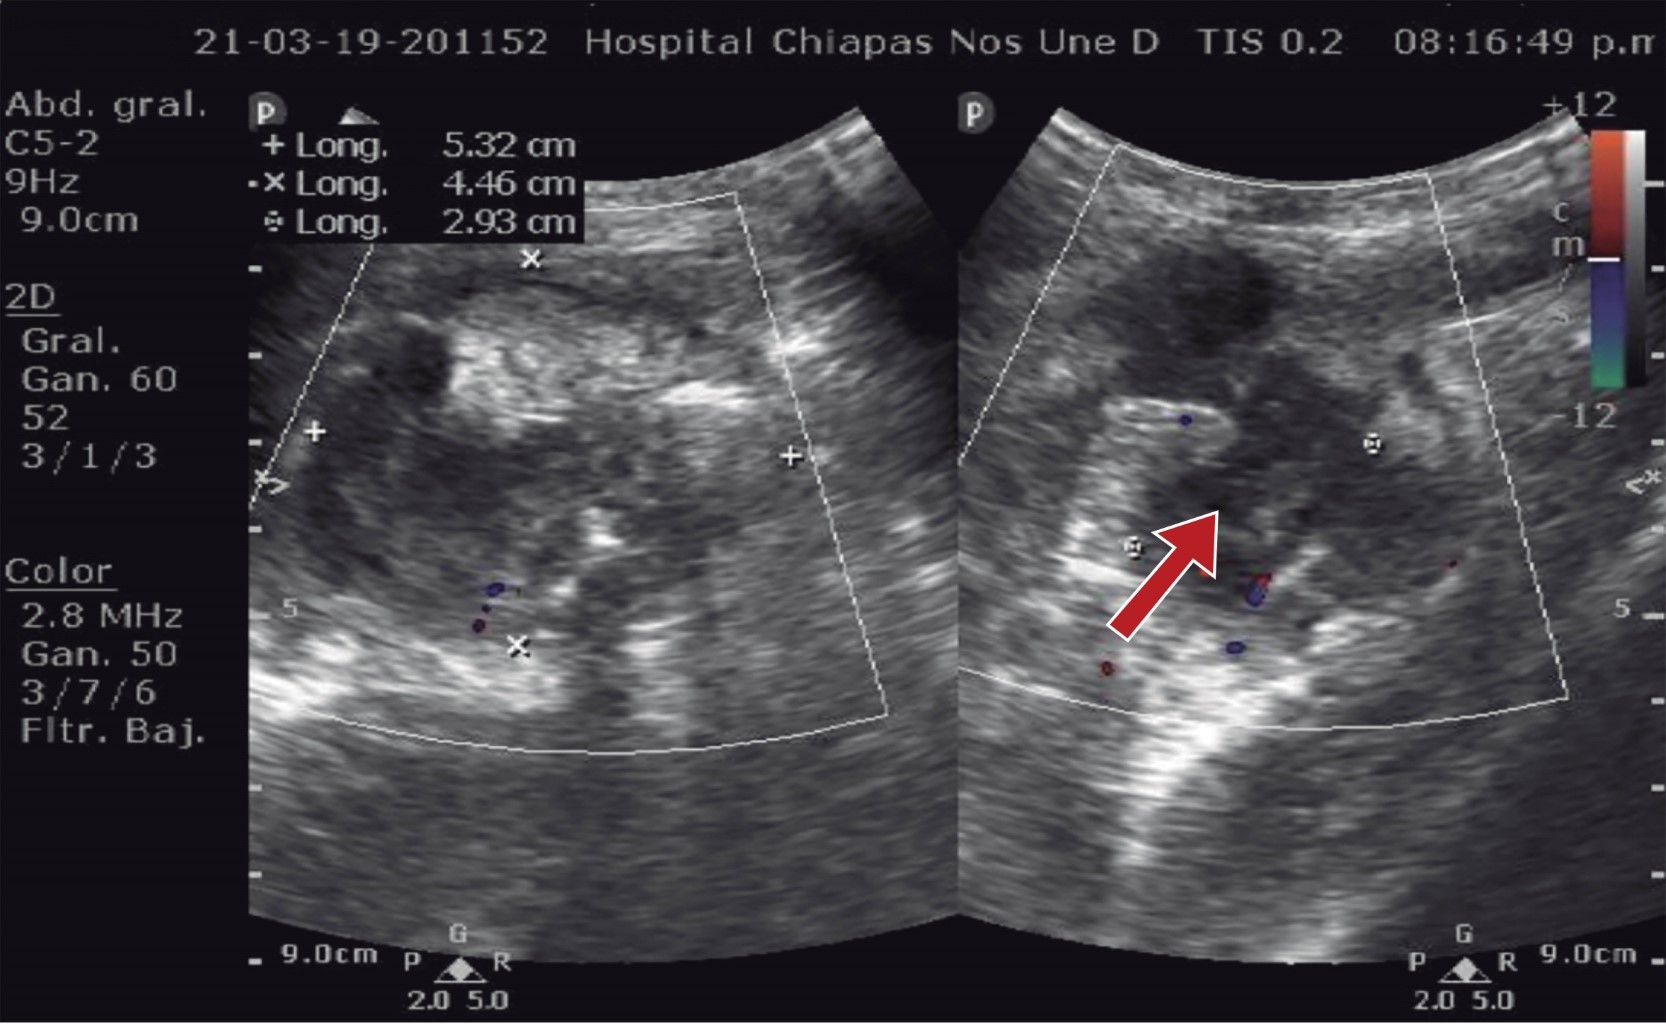

Masculino de nueve años con antecedente de haber sido intervenido quirúrgicamente por apendicitis aguda dos años y medio previos a su padecimiento actual, el cual inicia 10 días antes de su ingreso y se caracteriza por dolor abdominal generalizado y vómitos en dos ocasiones de características gastroalimentarias, manejado por facultativo con analgésicos no especificados y sin mejoría. Continúa con dolor abdominal de predominio en el cuadrante inferior derecho acompañado de náuseas y vómitos. Motivo por el cual acude al Servicio de Urgencias del hospital, en donde se encuentra al paciente con dolor en cuadrante inferior derecho, posición en gatillo y con datos de irritación peritoneal. Se solicitan laboratoriales, reportándose hemoglobina de 13.0 mg/dl, hematocrito de 38.2%, 15.15 × 109, 76.4% neutrófilos. La placa simple de abdomen muestra una imagen de asa fija en fosa iliaca derecha (Figura 1). Se solicita ultrasonido abdominal, el cual reporta una colección de 5 × 4 cm (Figura 2), por lo que se interconsulta al Servicio de Cirugía General ya que no se contaba con cirujano pediatra en el turno; 24 horas después de su ingreso es valorado por cirugía, encontrando al paciente con discreta resistencia voluntaria en cuadrante inferior derecho e irritación peritoneal. Se solicita una resonancia magnética abdominal, para determinar la probable etiología de la colección, la cual reporta una colección amorfa en fosa iliaca derecha, de bordes irregulares y bien definidos, con medidas de 5.1 × 4.3 × 4.9 cm en sus diámetros longitudinal y anteroposterior transverso, respectivamente, compatibles con absceso en fosa iliaca derecha.

Los estudios de imagen, como el ultrasonido y la tomografía, suelen ser de gran ayuda para orientar al diagnóstico. El ultrasonido tiene una sensibilidad y especificidad de 44 y 93% respectivamente y la tomografía computarizada una sensibilidad y especificidad de 97 y 94%, respectivamente.5,11

El estudio de ultrasonido podría detectar un crecimiento del tamaño del muñón, evidenciar la presencia de líquido libre en fosa iliaca derecha y edema en el ciego;12,13 mientras que la tomografía computarizada puede mostrar cambios inflamatorios en la región pericecal, engrosamiento de la pared del ciego (signo de la punta de flecha), presencia de líquido en la zona pericecal y paracólica e incluso demostrar la presencia de una estructura tubular relacionada con el ciego o hasta el apendicolito.14

Figura 2